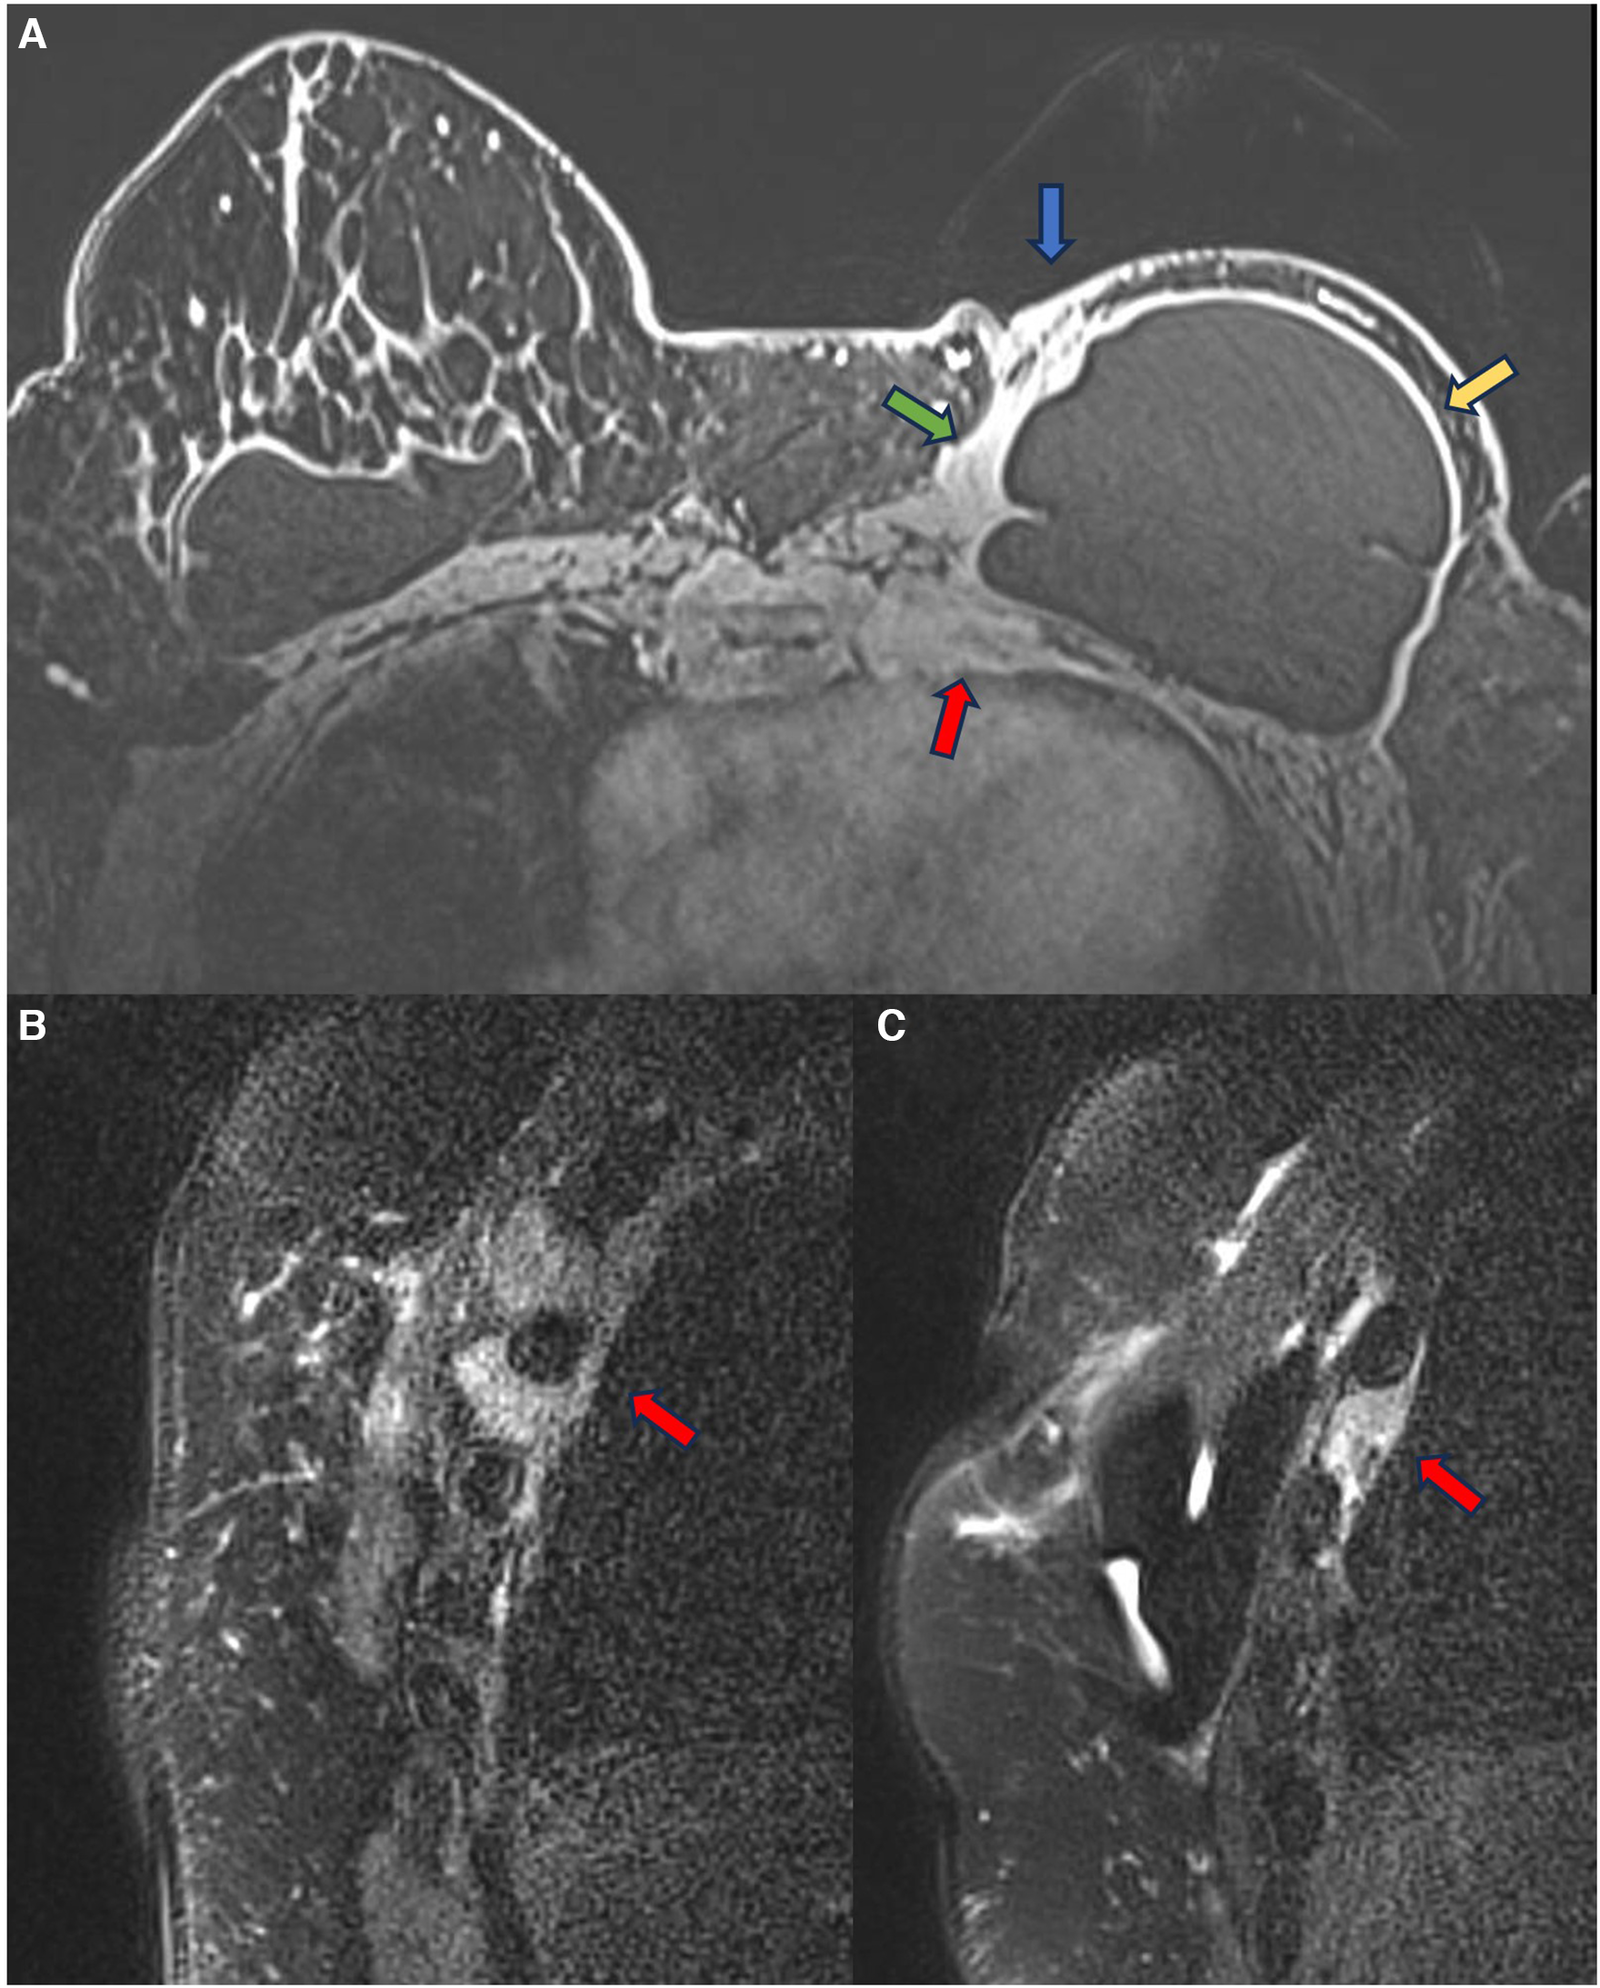

In episodes of recurrent/remitting acute inflammation, the established chronic inflammatory process can extend to the thoracic wall structures, involving the ribs, intercostal musculature, and costosternal joints. Magnetic resonance imaging is the best method to assess the involvement of the chest wall and allows for distinguishing the compromised structures by the inflammatory process (Figure 5). The differential diagnosis in this situation is malignant neoplasia, especially sarcomas and desmoid tumors, thus having the convenience to continue the clinical investigation in the presence of a pericapsular inflammatory process of the chest wall (27, 28).

Figure 5. A 48-year-old woman with reconstructive retropectoral silicone for 6 years. Axial T1 post-contrast image (A) and sagittal T1 post-contrast images at different sites (B,C) show a left capsular contracture associated with edema (yellow arrow). There is contiguity of the fibrous capsule to the pectoral muscle (green arrow) and the skin (blue arrow). The inflammatory process also extends to the thoracic wall, involving the ribs and intercostal muscles.